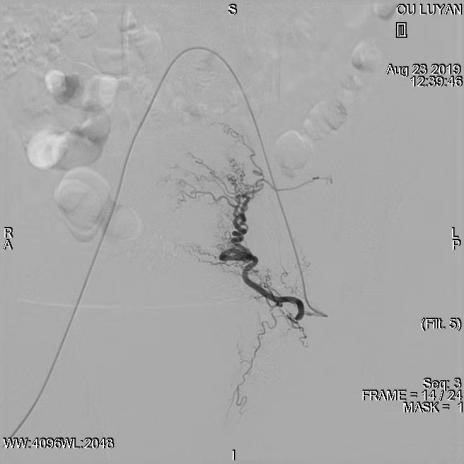

综合评估后考虑患者为Ⅱ型子宫切口妊娠,与患者及家属沟通后决定选择药物杀胚同时行双侧子宫动脉栓塞术。DSA显示双侧子宫动脉增粗、迂曲,均注入150-560um明胶海绵颗粒,造影显示栓塞满意。血β一HCG下降后在宫腔镜、B超引导下清除妊娠病灶,积极终妊。8月27日,手术过程进行顺利,未输血,患者于9月1日出院,后期继续加强康复治疗,预防远期并发症宫腔粘连发生。

左侧子宫动脉增粗、迂曲

栓塞术后左侧子宫动脉未见显影

右侧子宫动脉稍增粗、迂曲

栓塞术后右侧子宫动脉未见显影